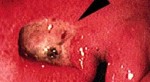

Nguyên nhân, dấu hiệu và cách điều trị bệnh giang mai ở nam giới

Giang mai ở nam giới là một bệnh truyền nhiễm do xoắn khuẩn giang mai gây ra và lây truyền qua tiếp xúc trực tiếp, thường là thông qua quan hệ tình dục.